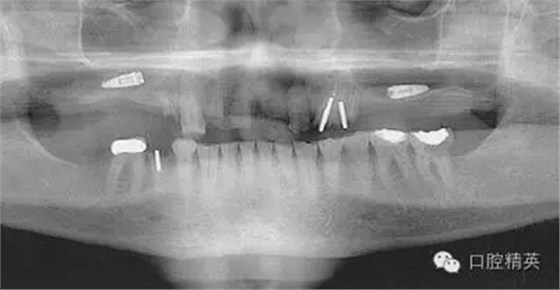

圖4:兩維曲面斷層影像難以獲得精確定位,有的醫(yī)生為了避免損傷下頜神經(jīng)管而應(yīng)用短種植體。這樣做的結(jié)果是增加了修復(fù)體-種植體長(zhǎng)度比,隨著時(shí)間的流逝會(huì)造成骨吸收,最終可能導(dǎo)致種植體折斷。骨內(nèi)折斷的種植體片斷需要手術(shù)取出,然后進(jìn)行植骨,骨質(zhì)愈合后再次種植,這些步驟不僅創(chuàng)傷大,而其從心理和經(jīng)濟(jì)上都會(huì)對(duì)患者造成損失。

如這個(gè)病例展示的,CBCT斷層掃描揭示了牙槽骨根方的凹陷。這樣就避免了術(shù)中的意外,醫(yī)生可以在術(shù)前完善的計(jì)劃,向患者交代清楚手術(shù)方法、風(fēng)險(xiǎn)、以及植骨所需增加的相應(yīng)費(fèi)用等問(wèn)題。在兩維的放射影像中是無(wú)法預(yù)先觀察到這個(gè)問(wèn)題的。僅使用兩維放射診斷帶來(lái)的另一個(gè)并發(fā)癥是種植體折斷。(圖4)前面提過(guò),兩維曲面斷層影像難以獲得精確定位,有的醫(yī)生為了避免損傷下頜神經(jīng)管而應(yīng)用短種植體。這樣做的結(jié)果是增加了修復(fù)體-種植體長(zhǎng)度比,隨著時(shí)間的流逝會(huì)造成骨吸收,最終可能導(dǎo)致種植體折斷。

這種情況發(fā)生時(shí),骨內(nèi)折斷的種植體片斷需要手術(shù)取出,然后進(jìn)行植骨,骨質(zhì)愈合后再次種植,這些步驟不僅創(chuàng)傷大,而其從心理和經(jīng)濟(jì)上都會(huì)對(duì)患者造成損失。關(guān)于修復(fù)體—種植體高度比的問(wèn)題也常導(dǎo)致修復(fù)醫(yī)生和外科醫(yī)生之間的爭(zhēng)執(zhí)。我們將在后面關(guān)于物理機(jī)械原因?qū)е碌姆N植體失敗模式的章節(jié)中進(jìn)一步討論關(guān)于修復(fù)“冠根”比的概念。